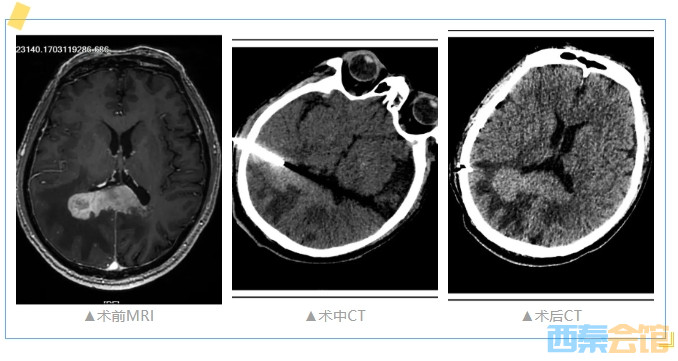

近日,川南中西医结合肿瘤防治中心联合外科在麻醉科的护航下成功完成了我院首例CT定位下颅内肿瘤穿刺活检术。

颅内肿瘤穿刺活检术在我院尚属首例,且穿刺手术本身就存在极大的风险,加上患者的基础疾病,风险陡然增加。经与患者及家属沟通同意后,1月4日,肿瘤血液科、外科、麻醉科通力协作下行CT定位下颅内肿瘤穿刺活检术,手术顺利取得组织标本,术中、术后无出血等并发症,术后患者无特殊不适。

1月5日,颅内肿瘤穿刺活检病理提示小细胞恶性肿瘤,拟进一步行免疫组化后选择最佳治疗方案。